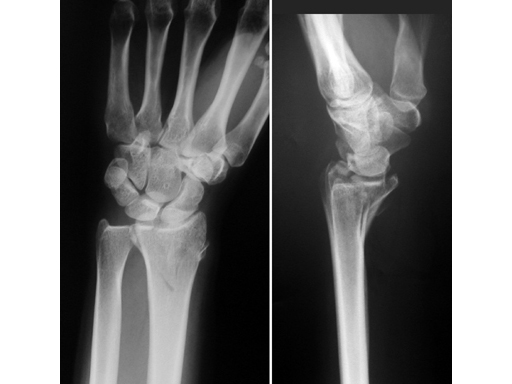

The Locking Distal Radius System 2.4 consists of the new plates: LCP T-Plate 2.4, LCP Radial Column Plate 2.4, LCP L-Plate 2.4, LCP Distal Radius Plate 2.4, dorsal (p-Plate), LCP Volar Plate 2.4, and LCP Volar Buttress Plate 2.4. The 2.4 mm Locking Head Screw, self-tapping, the 2.4 mm Cortex Screw, self-tappingboth with Stardrive recessand special instruments complete the new system. This variety of plates allows fragment-specific treatment of all patterns of distal radial fractures. Indications are simple and displaced extraarticular and intraarticular distal radial fractures and corrective osteotomies of the distal radius. All implants are manufactured in Ti15Mo resulting in excellent bending properties and resistance to fatigue failure, allowing reverse bending. The edges of all plates are chamfered to reduce sharp edges that could contribute to irritation of tendons. Surfaces are polished to minimize tissue adhesion. The distal arms provide a smooth gliding surface for the tendons. Different plate lengths are offered to avoid cutting. The angular stability of the construct allows treatment of osteoporotic bone.